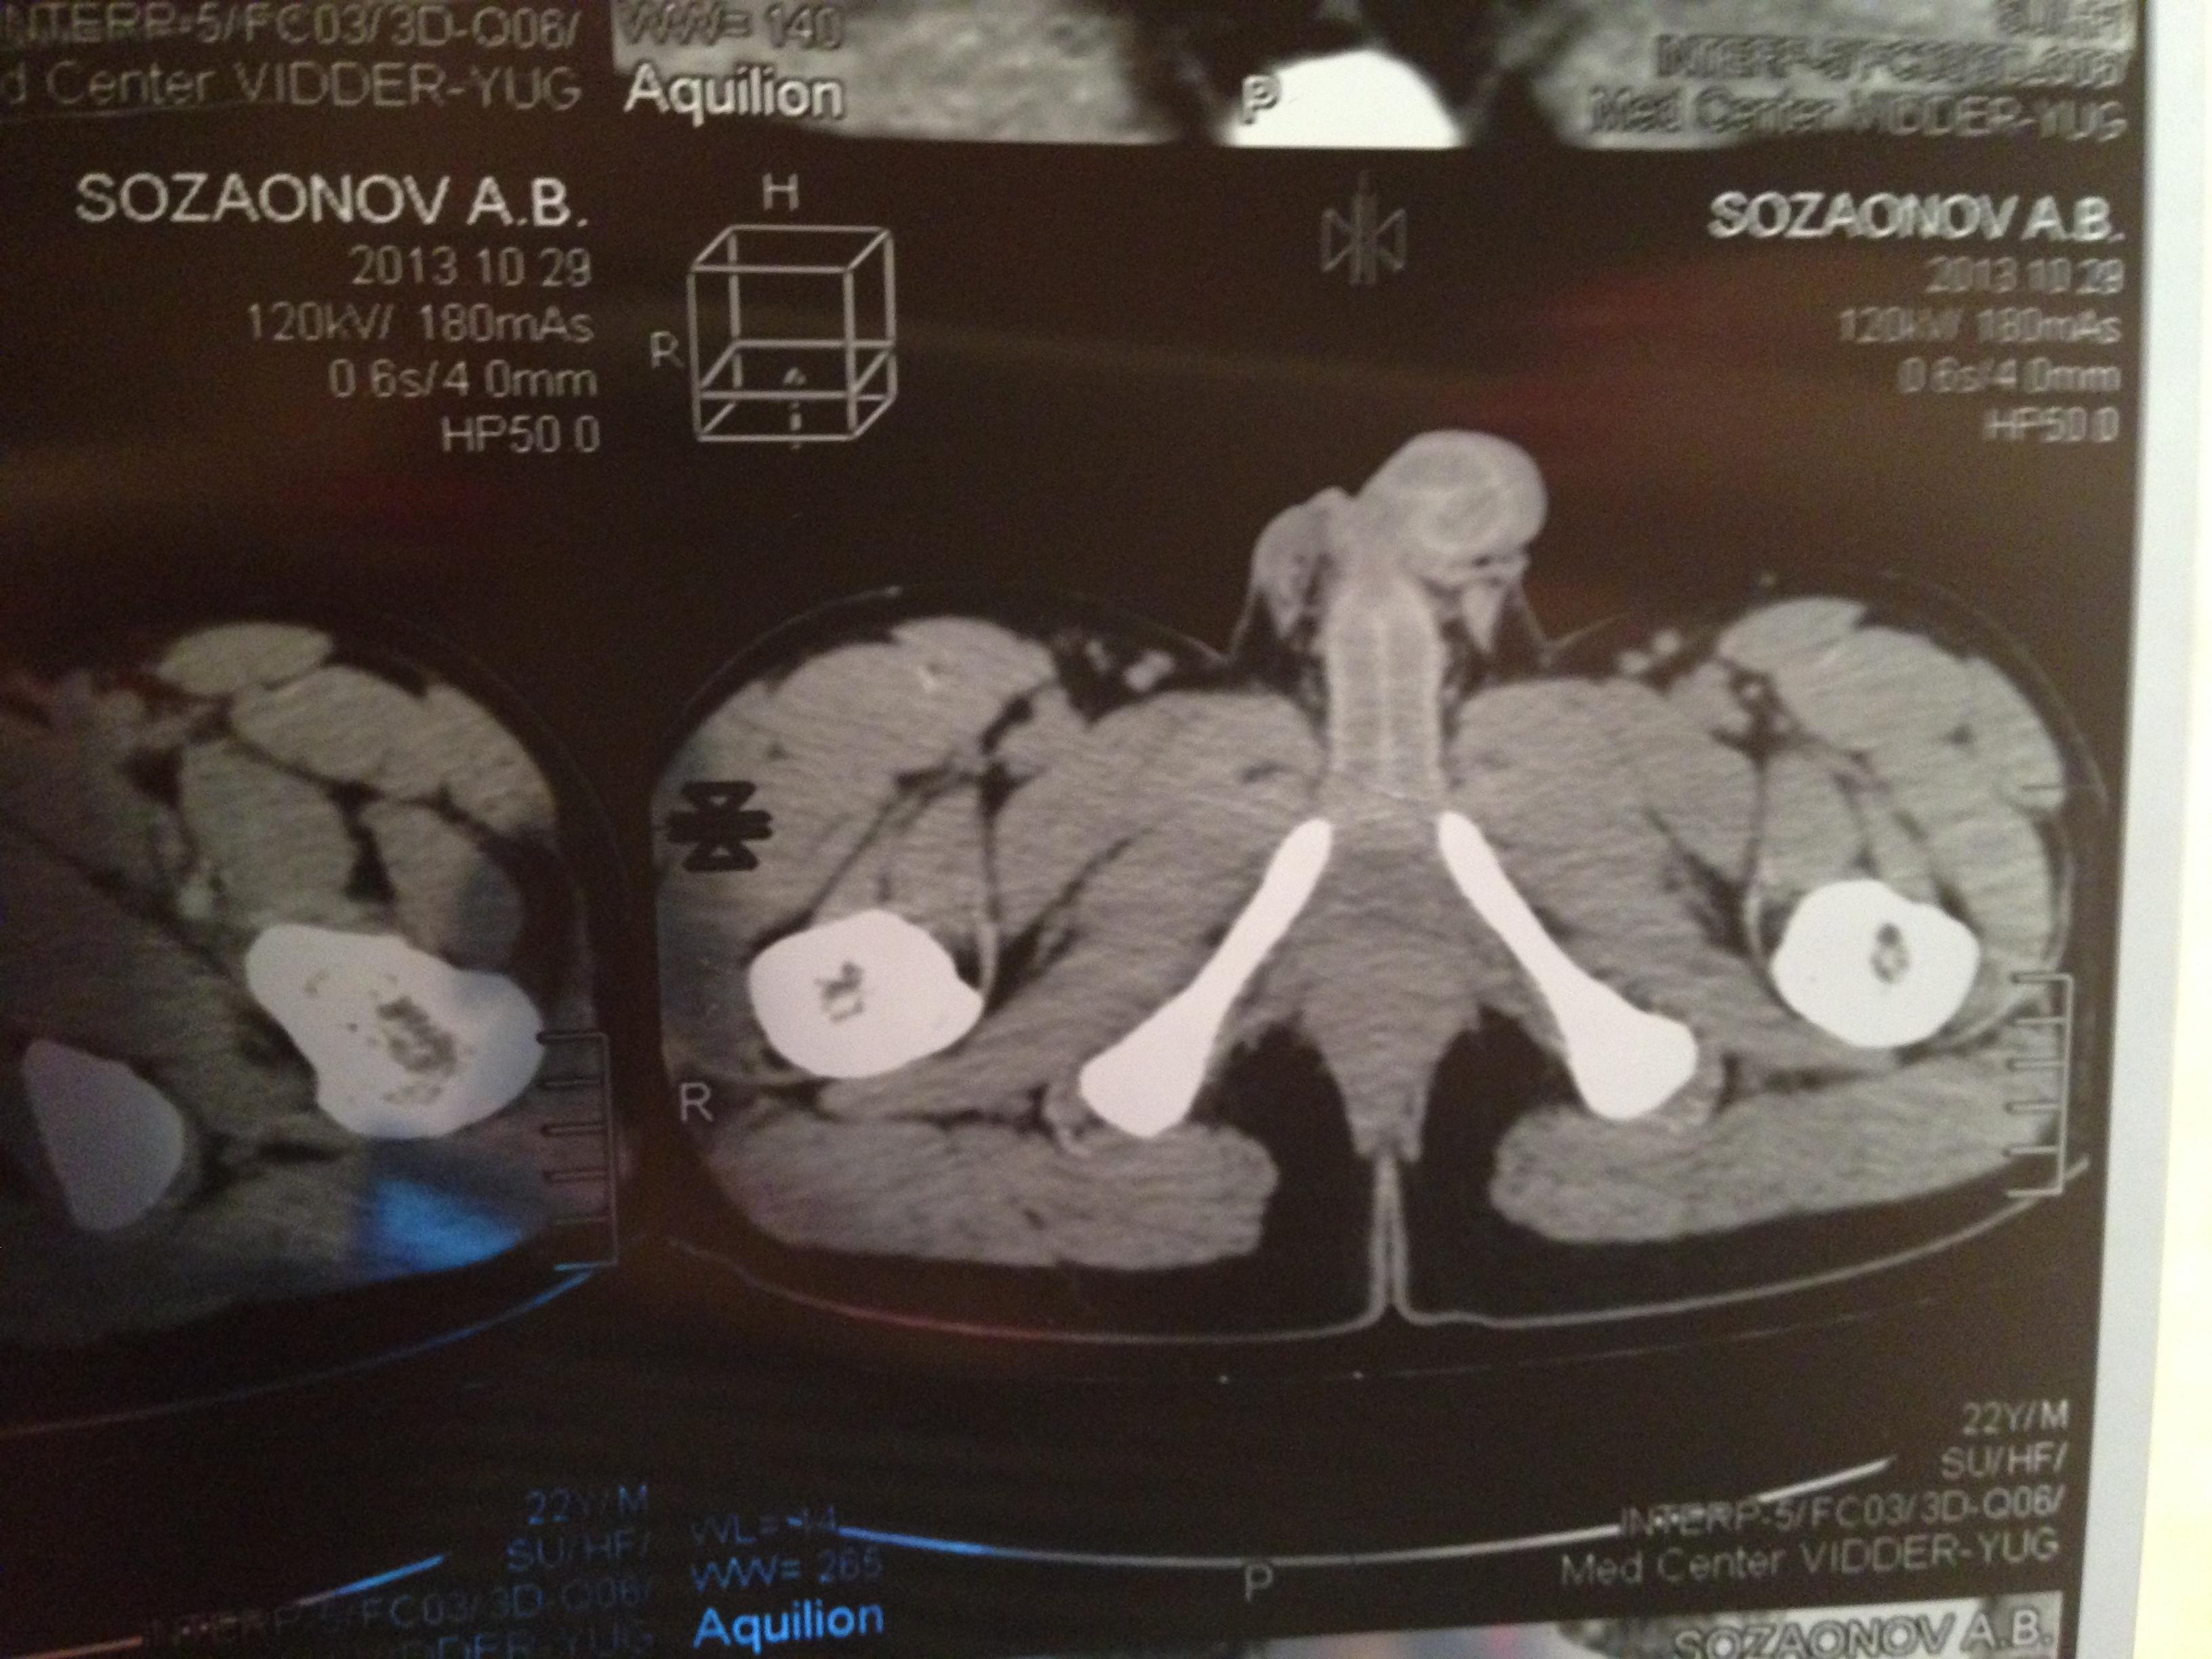

проведена МСКТ области таза!Внеорганных дополнительных патологических образований,лимфаденопатии или свободной жидкости в области таза не выявлено.

Мочевой пузырь-наполнен,стенки не утолщенны,паравезикально-без грубой органки.

Граница между предстательной железой и пузырем несколько четкая,контур пузыря на данном уровне не деформирован.

Предстательная железа-без грубой органики,еденичные микрокальцинаты.

Семенные пузырьки-конфигурация не совсем типична,примерный размер правого 26*28мм.Отмечаются признаки кистовидной трансформации и микрокальцинации обоих пузырьков.Наибольшая из кист слева достигает 9 мм.Обращает на себя внимание неравномерная кальцинация стенок крупных регионарных(текстикулярных)артерий с обоих сторон.

Костно-деструктивных изменений характерных для mts со стороны костей таза не отмечено.

Параректальная клетчатка-не изменена,патологически увеличенных лимфоузлов в параректальном пространстве не отмечено.M.m.levator ani-без особенностей.

Заключение:на момент исследования,КТ-данных за наличие внеорганных дополнительных патологических образований,лимфоденопатии или свободной жидкости в области таза не выявлено.КТ-признаки в пользу проявлений калькулезного везикулита с элементами кистовидной трансформации семенных пузырьков.